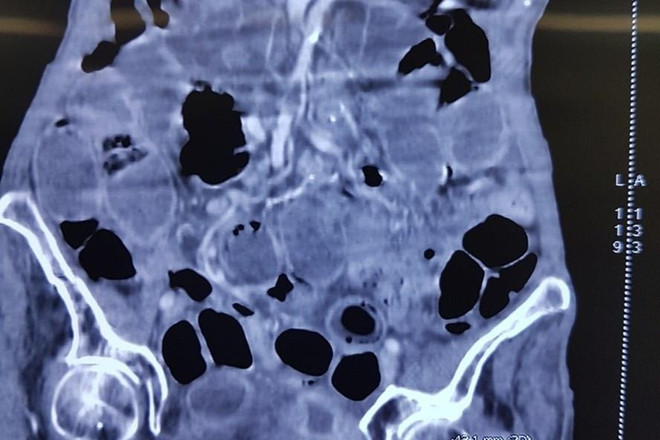

Cứu sống một cụ bà 90 tuổi bị thủng ruột do bệnh lý hiếm gặp ảnh 1Hình ảnh chụp CT của bệnh nhân.

Qua thăm khám và chụp cắt lớp vi tính ổ bụng, bệnh nhân được chẩn đoán là tắc ruột do thoát vị bịt nghẹt bên trái ngày thứ 12.

Trên hình ảnh cắt lớp vi tính có hình ảnh mức khí-dịch trong hố bịt trái nghi đã hoại tử ruột, gây áp xe hố bịt, nguy cơ phải cắt đoạn ruột.